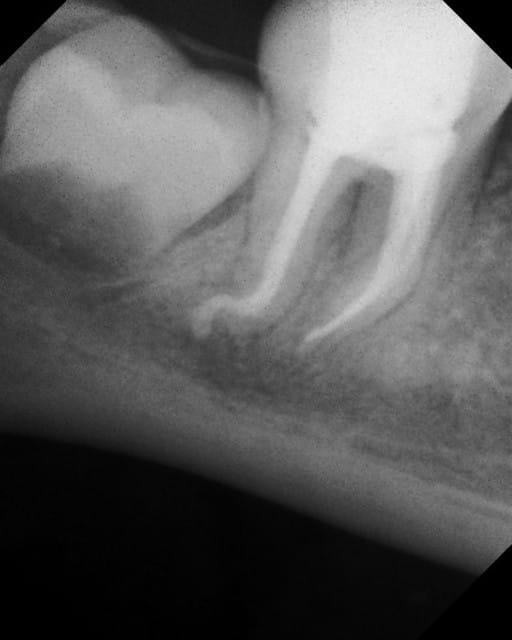

19/01/2011 à 19h52

Tubli-seal EWT Xpress Kerr.

Je viens juste de faire ça avec (et surtout de la gutta quand même)

Tubli seal e9zj4f - Eugenol

X04908 bfss1q - Eugenol